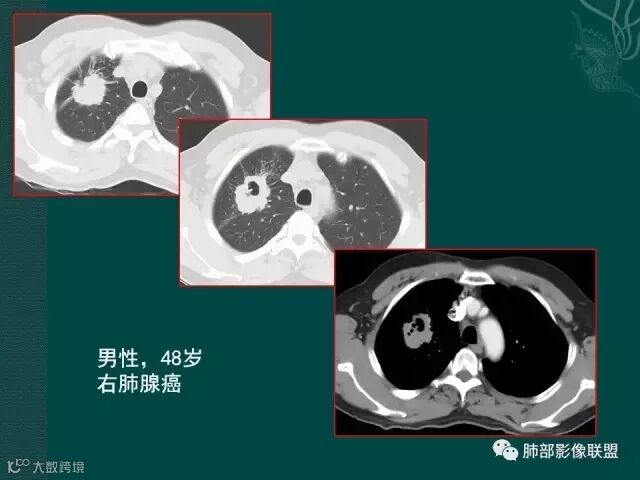

第一个是肺腺癌,边缘有毛刺,多发小空泡,直径不到5mm;

第二个是典型的肺癌坏死后形成的厚壁空洞;

第三个也可以称为空洞,但和第二个不完全相同,壁较薄,内有分隔,我们也称为假性空洞,是支气管活瓣作用形成的,我们也称为假大空。